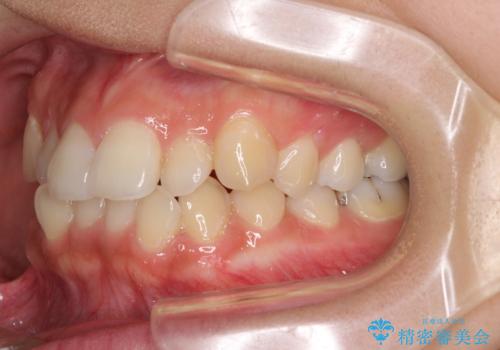

前歯の突出感とデコボコ インビザラインで改善

- 上下前歯のデコボコを気にして来院された患者様です。

インビザラインによる上下歯列の側方拡大と後方移動、IPR(歯と歯の間を削る)にるスペースの獲得により歯列を整えることとしました。

右上の小臼歯は歯根癒着をしており、様々な方法を試みるも動かすことができませんでした。

それでも奥歯のかみ合わせに不自由はなく、歯列をきれいに整えることができました。